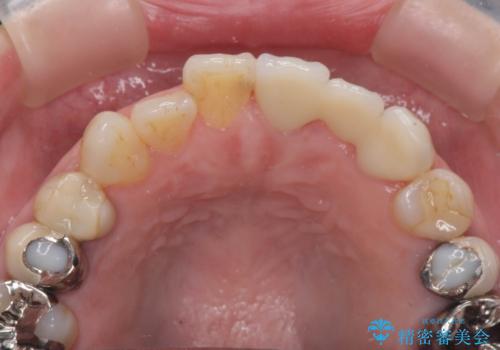

- 39.6万円(ジルコニアクラウン×3・仮歯×3)費用は治療当時の料金となります

精度、周囲の歯の色調にこだわったオールセラミックブリッジを作製し、しっかりと機能・審美性を改善することができました。